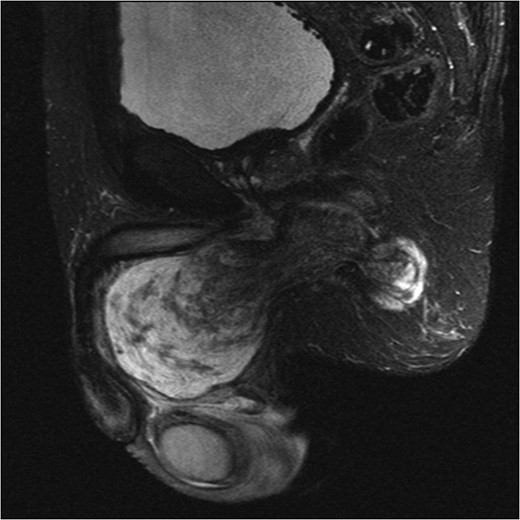

An initial ultrasound confirmed a well-defined heterogenous encapsulated solid mass with internal vascularity. An abdominopelvic MRI revealed a 5.4 cm × 7.2 cm × 15.7 cm solid-cystic well-defined lobulated mass within the perineum separate from the testicles, adjacent to the penis and extending to the right ischial fossa and the obturator internus muscle (Fig. 1). Anteriorly the mass displaced the penile urethra and bulb and the anal sphincters without direct involvement (Fig. 2). There was no locoregional or para-aortic lymphadenopathy.

MRI abdomen and pelvis T2 weighted sequence sagittal view showing a predominantly cystic mass with scattered solid components within perineum.